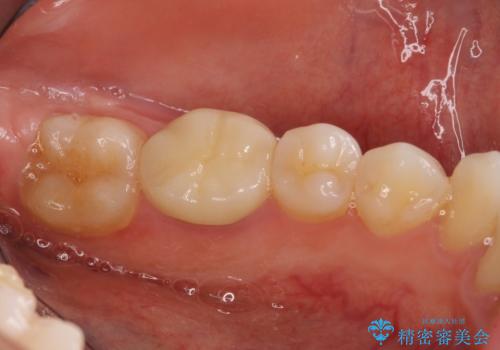

海外転勤が決まり、急いでセラミック治療をしてほしいとご来院された患者様です。

根管治療に症状がなく、上の歯に関しては土台もそのまま使用可能であったため、下の歯の土台、上下の歯のセラミック治療を行いました。

今回は幸い、症状がなく、根管治療の再治療が必要でないため、円滑に治療を進めることができました。